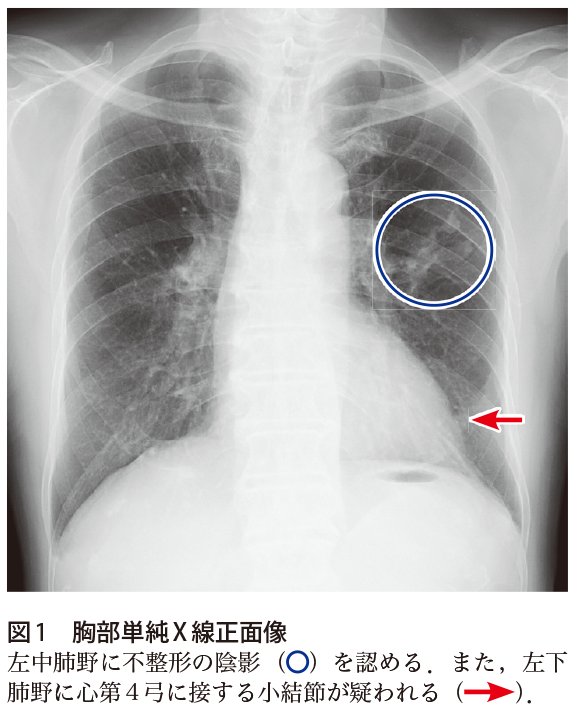

解答 解説 健診で異常を指摘された80歳代男性 実践 画像診断q A 羊土社 レジデントノート 羊土社